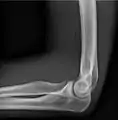

- Elbow - AP and Lateral. Radial head projections available on request

Lateral projection

Anteroposterior projection

Left elbow by 30 degrees internal oblique projection

Left elbow by 30 degrees external oblique projection